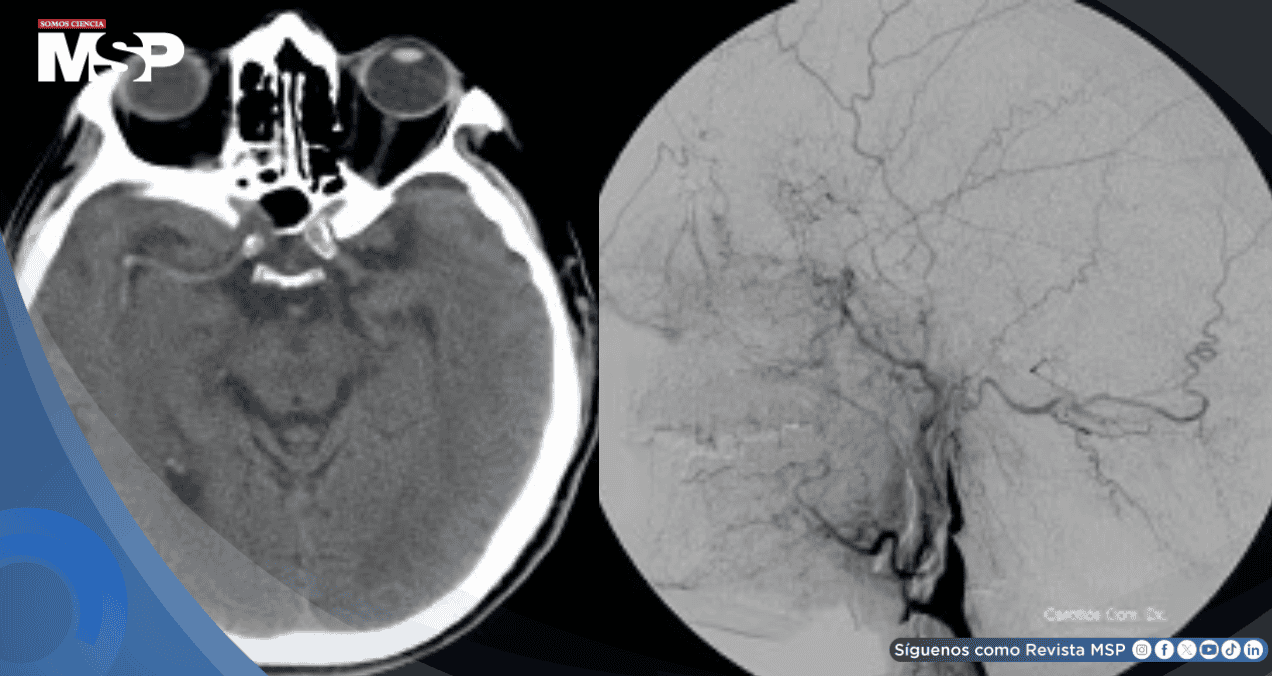

Las pruebas de imagen resultaron cruciales para confirmar las sospechas clínicas. La tomografía computarizada cerebral inicial mostró signos de obstrucción arterial, mientras la angiografía, un estudio especializado de los vasos sanguíneos, reveló el estrechamiento característico de la arteria carótida con la apariencia de "cola de rata" que confirmaba definitivamente la disección arterial.

Estudios complementarios como el ultrasonido carotidéo también mostraron la estrechez vascular, completando el panorama diagnóstico.